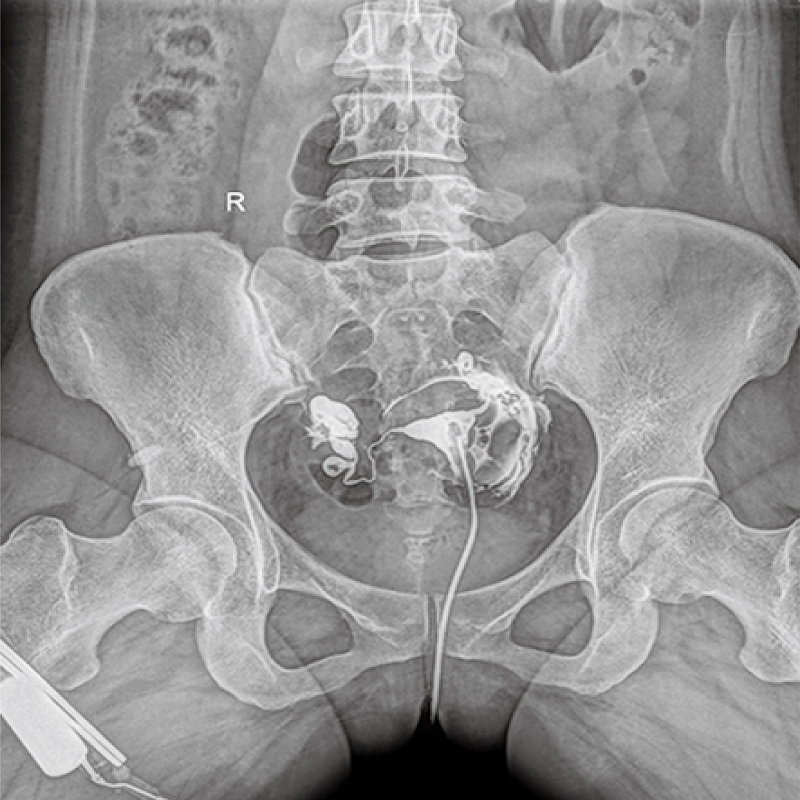

多功能、全視角、真視界,全面突破傳統(tǒng)X線攝影透視理念,通過(guò)一塊新型動(dòng)態(tài)平板探測(cè)器,在檢查中既可實(shí)現(xiàn)數(shù)字透視又可實(shí)現(xiàn)數(shù)字?jǐn)z影,還可做數(shù)字胃腸及數(shù)字造影檢查。

● 只需一塊動(dòng)態(tài)平板探測(cè)器,高效輕松實(shí)現(xiàn)攝影、透視和造影功能,幾乎可以滿足醫(yī)院全科室

● 大功率高頻高壓發(fā)生器,X射線硬度強(qiáng),穩(wěn)定性高,穿透性強(qiáng),輕松應(yīng)對(duì)體型肥胖的檢查者

● 原裝進(jìn)口大熱容量的高速X線管、雙焦點(diǎn)配置、持續(xù)工作時(shí)間更長(zhǎng),滿足大流量的臨床檢查需求

● 按照1米和1.8米兩個(gè)標(biāo)準(zhǔn)體位配置2塊可移除式濾線柵,過(guò)濾掉更多的散射線,專距專用